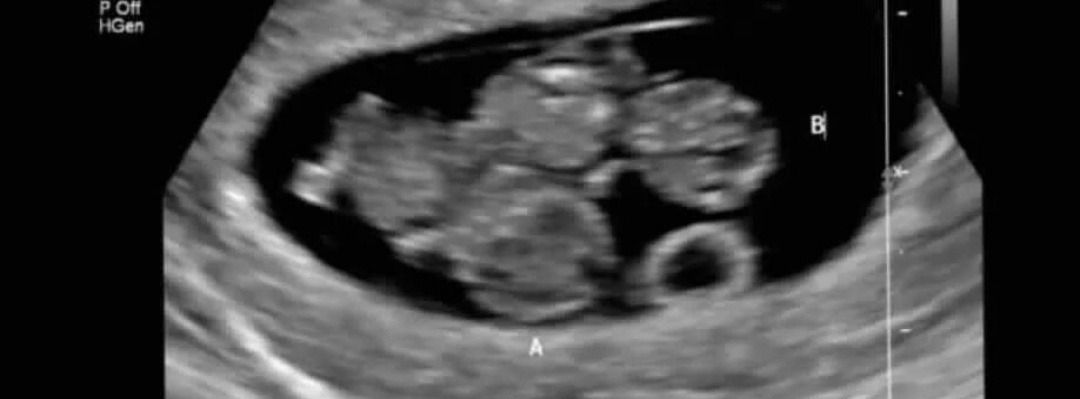

После нескольких потерь мы с мужем решились на ЭКО. Вторая попытка подарила нам две полоски. На УЗИ увидели два желточных мешка в одном плодном яйце — эмбрион поделился. Это была монохориальная моноамниотическая двойня (одна плацента и нет перегородки между малышами) — большая радость и огромный риск. Мы боялись, но уже начали вглядываться в коляски-«паровозики» и читать про жизнь с двойней.

Мальчики росли хорошо, но на первом же скрининге прозвучал приговор: «Если доносите до 22 недель — это удача». Я наблюдалась в лучшем профильном роддоме, сдавала анализы у гематолога, делала УЗИ. 3 сентября на очередном скрининге всё было прекрасно. А 5 сентября я уже не могла найти сердцебиения домашним доплером.